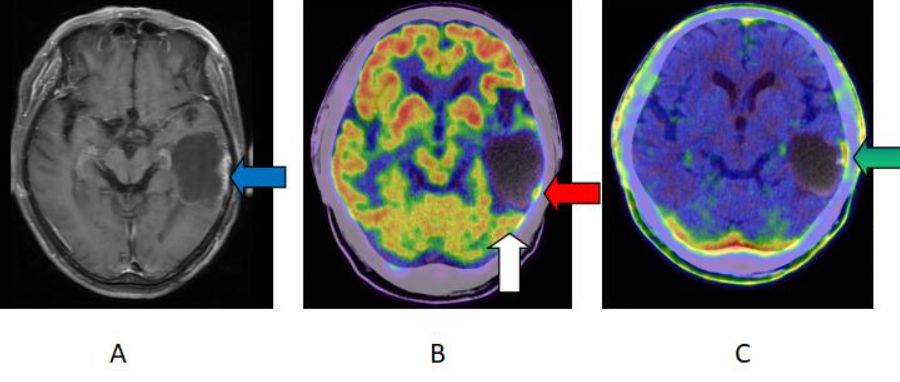

脑部蛋氨酸(11C-MET)PET显像是一种通过注射放射性标记的蛋氨酸来观察脑内肿瘤和异常活动的影像学检查技术。蛋氨酸是一种蛋白质组成部分,而PET显像则是一种核医学成像技术,能够显示脑内的代谢活动情况。结合使用这两种技术,医生可以更清晰地了解脑部肿瘤的位置、大小和代谢情况,有助于制定更为精准的治疗方案。

脑部蛋氨酸PET显像的原理其实并不复杂。在进行检查时,患者会先接受蛋氨酸的放射性标记剂注射,然后通过PET扫描仪对脑部进行成像。因为肿瘤细胞的代谢活动通常比正常细胞更加活跃,所以在PET图像上,肿瘤组织通常会显示出更高的代谢活动,从而与正常组织有所区分。

在进行脑部蛋氨酸PET显像前,医生会将一种放射性标记的蛋氨酸类似物注射到患者体内。这种放射性标记物会随后在体内发出特殊的信号,PET扫描设备能够捕捉到这些信号并根据其强度和分布情况生成相应的影像。通过这些影像,医生可以清晰地观察到脑部内蛋氨酸代谢的细微变化,从而判断出可能存在的异常情况。